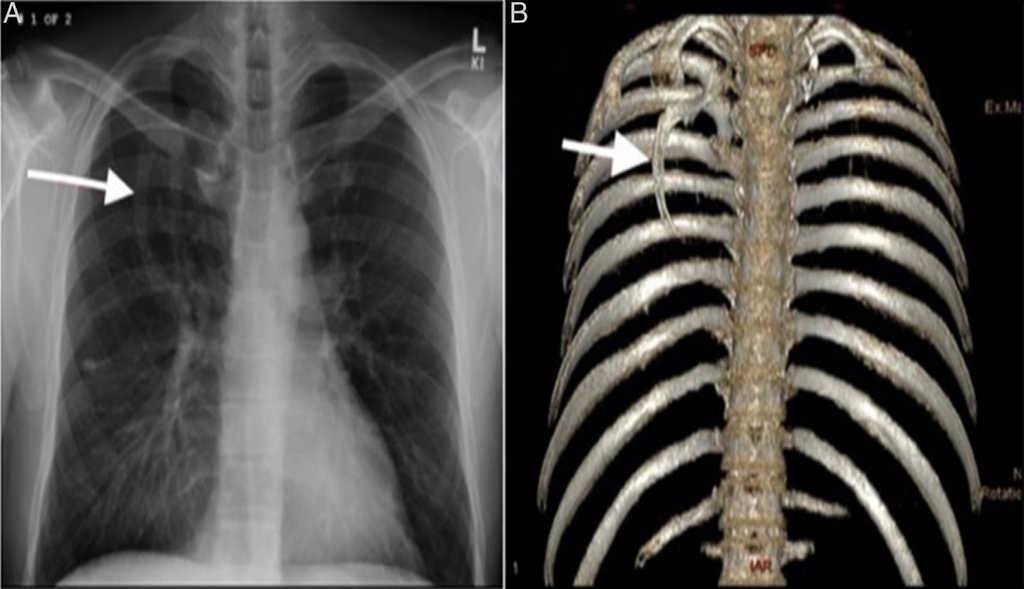

9. Баруун уушги нь зүүн уушгинаасаа илүү их агаар авдаг